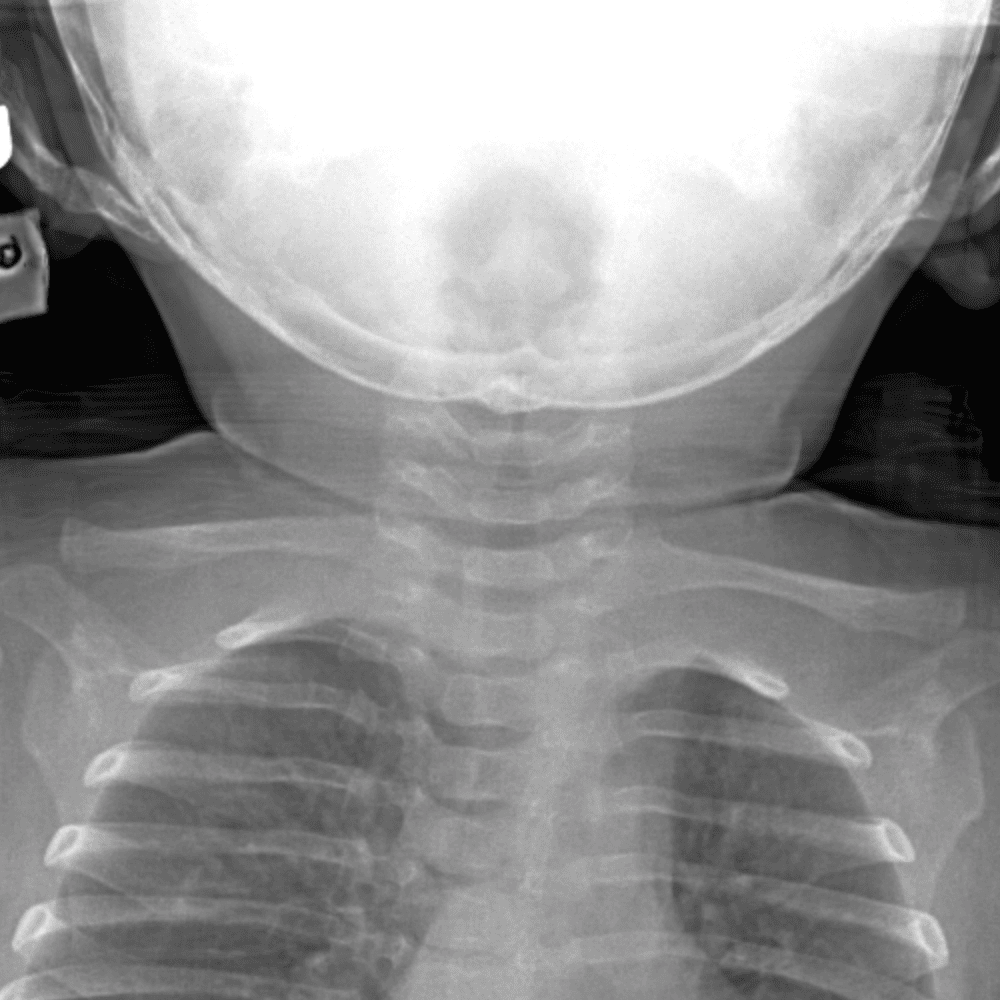

Peds Chest

Practice

Simulates call by including subtle or difficult cases and some normals.

50 cases